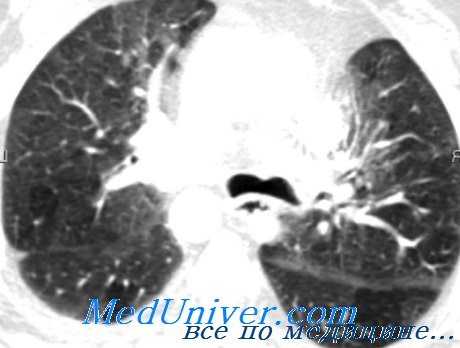

Симптомы опухолей бронхов

Наиболее яркая клиническая симптоматика развивается при эндобронхиальном росте опухоли, вызывающей нарушение бронхиальной проходимости. На стадии частичного бронхостеноза диаметр просвета бронха практически не изменен, пациента может беспокоить раздражающий кашель с небольшим количеством мокроты, изредка – кровохарканьем. Общее самочувствие не страдает. Рентгенологические признаки опухолевого роста отсутствуют; выявление новообразования возможно только с помощью КТ легких или бронхоскопии.

На стадии клапанного стеноза бронха опухоль уже в значительной мере перекрывает просвет воздухоносных путей. Больного беспокоит постоянный кашель с выделением слизисто-гнойной мокроты, кровохарканье, одышка, свистящее дыхание. Во время выдоха под давлением опухоль может полностью закрывать бронх, в связи с чем на этом этапе возникают признаки нарушения легочной вентиляции, воспалительные изменения. Рентгенологически обнаруживаются сегментарные инфильтраты, опухоль бронхов подтверждается эндоскопически или с помощью линейной томографии.

Полная обтурация бронха опухолью приводит к формированию ателектаза, нагноительных процессов в невентилируемом участке легочной ткани. Клиническая картина соответствует обтурационной пневмонии: лихорадка, кашель с гнойной мокротой, общая слабость, потливость. При аррозии бронхиальных сосудов могут возникать массивные легочные кровотечения.